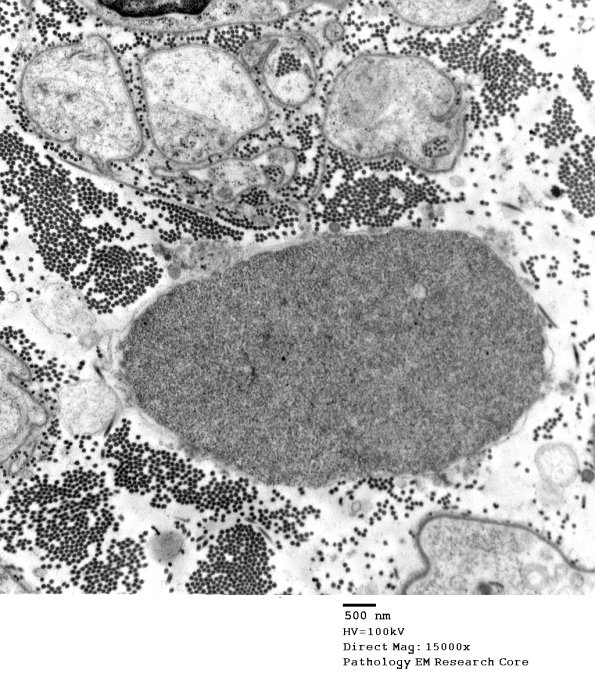

11D1,2 Dense collections make it difficult to recognize tubulovesicular substructure. (electron micrographs)